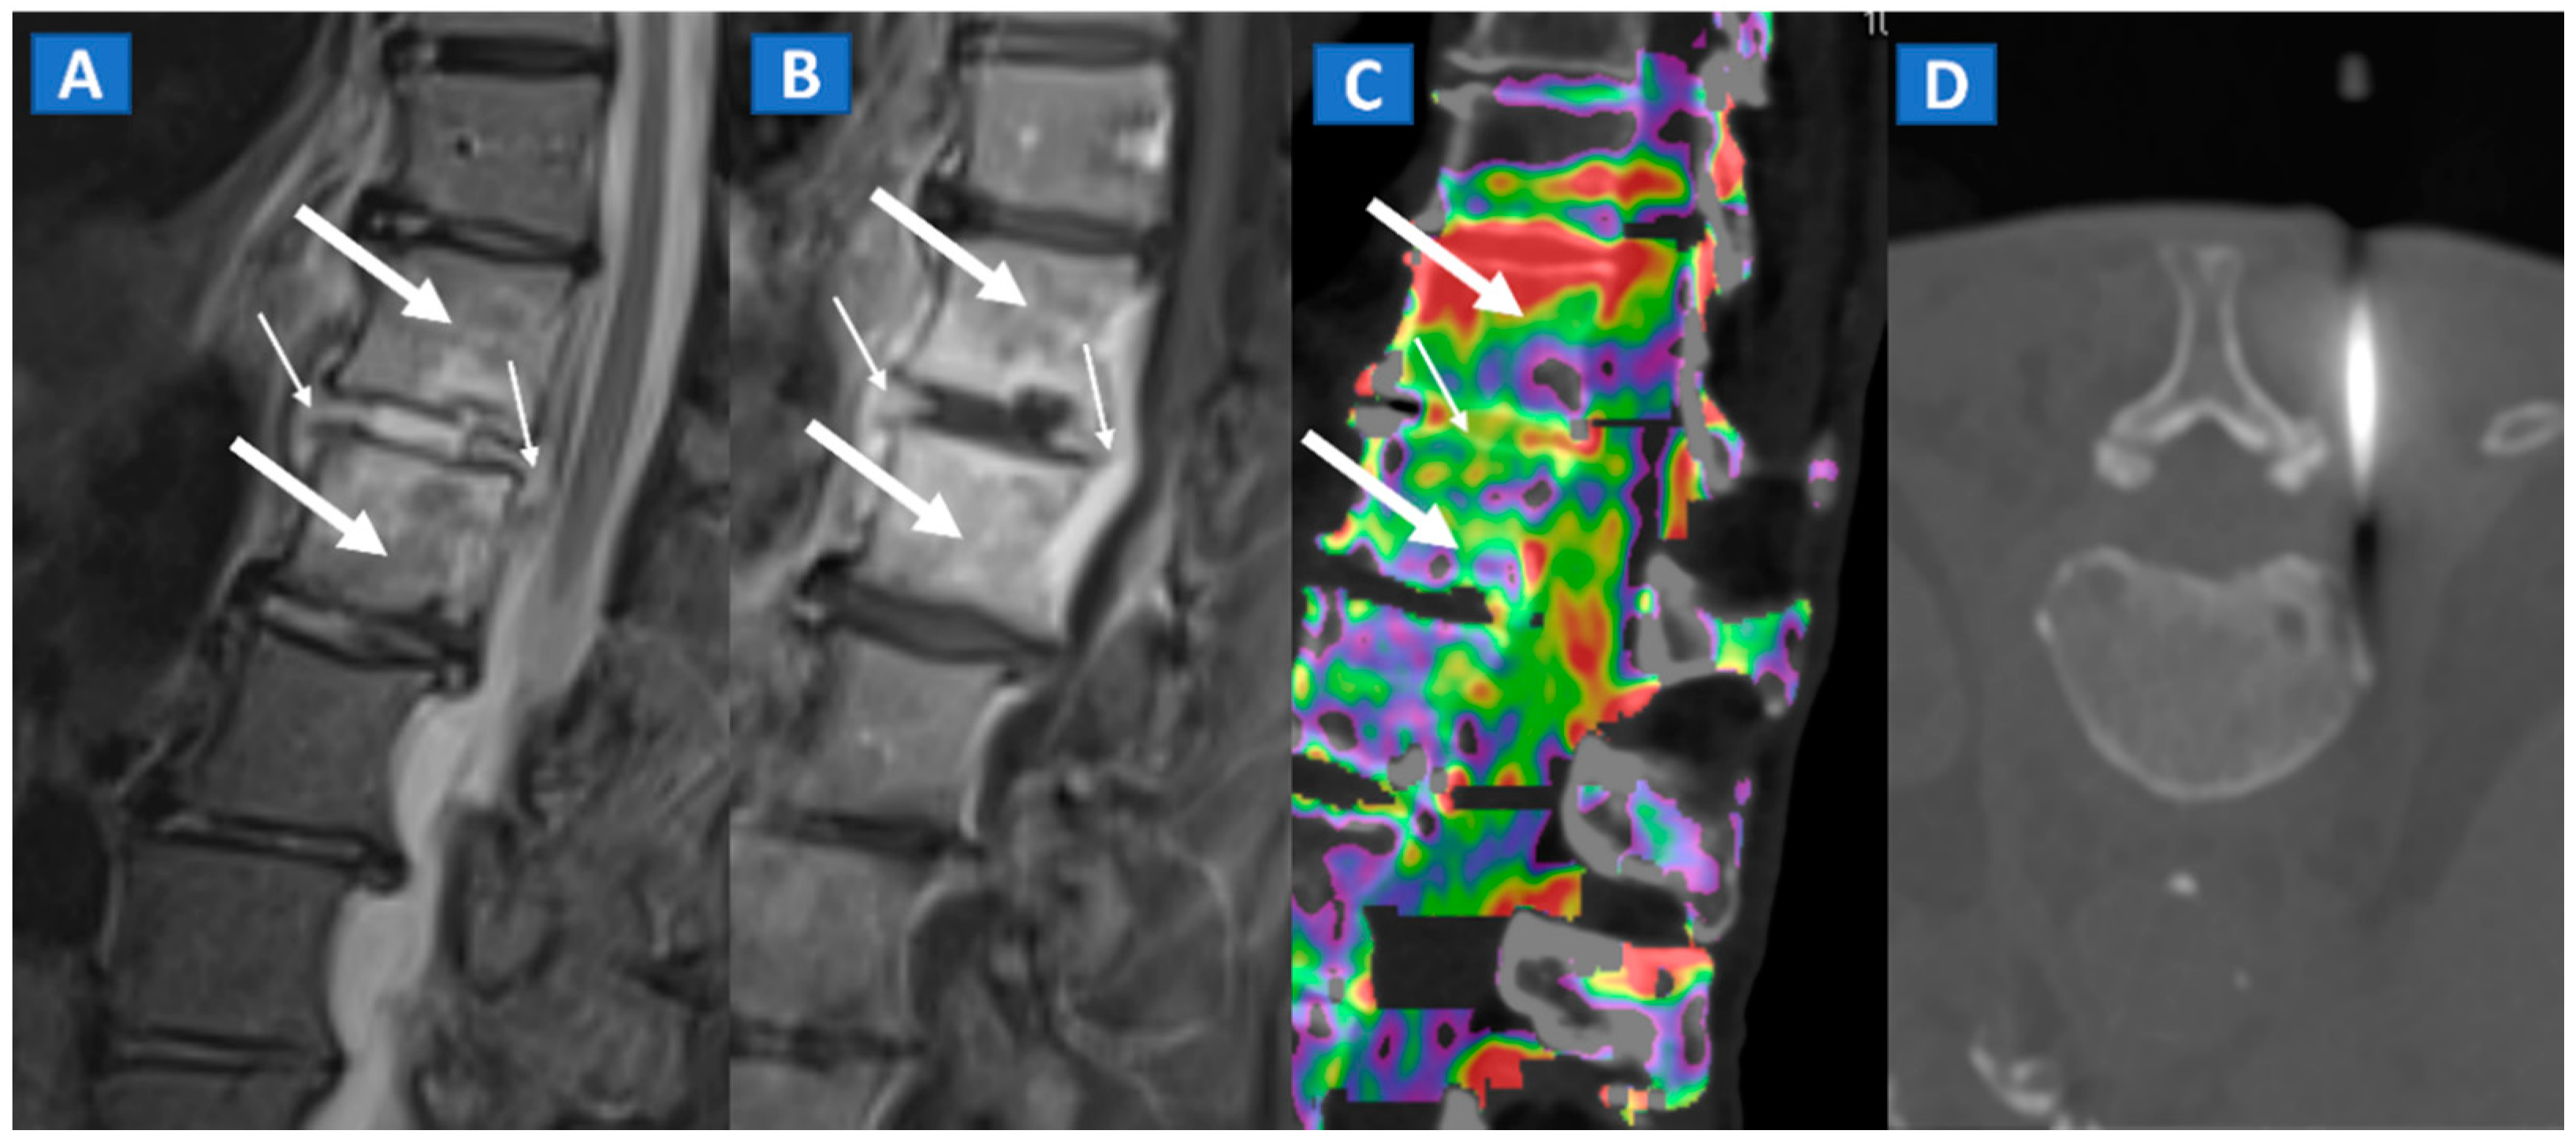

5. Vertebral Compression Fractures